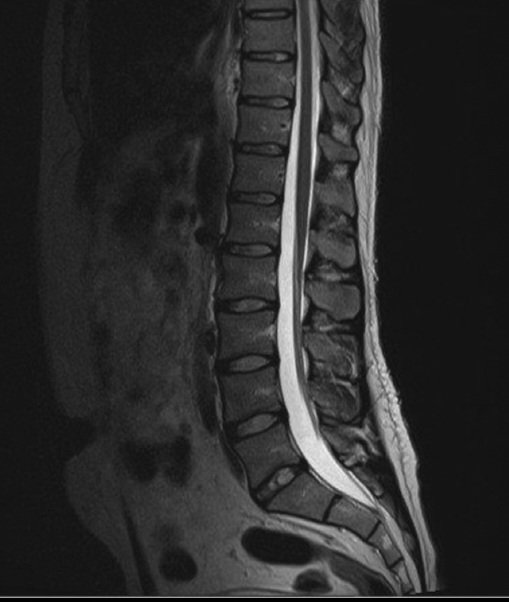

3- الرنين المغناطيسي( MRI):

-الأكثر دقة بين الاشعات في بعض الحالات.

-يأخذ صورة ثلاثية الأبعاد(3D).

-يستخدم في الحالات المرضية لى العمود الفقري والدماغ والعضلات والبطن.

-يستخدم مغناطيسًا قويًا وموجات الراديو في التصوير.

-لا يوجد إشعاع.

-مكلفة ماديا.

- تأخذ وقت أثناء التصوير.